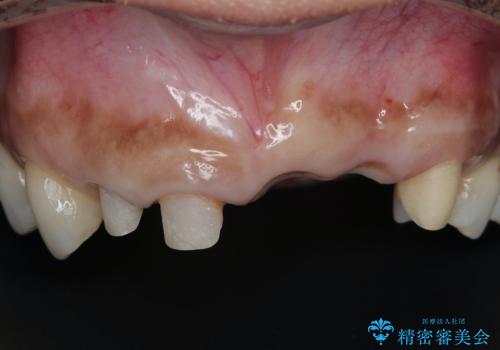

一見して問題ないように見える左側の2前歯は、セラミックを除去してみると亀裂や虫歯の再発が見られました。

抜歯時に可及的に歯肉のボリュームを保つよう骨充填材とコラーゲン製剤による填塞を行い審美的かつ機能的なブリッジとなるよう治療を進めます。